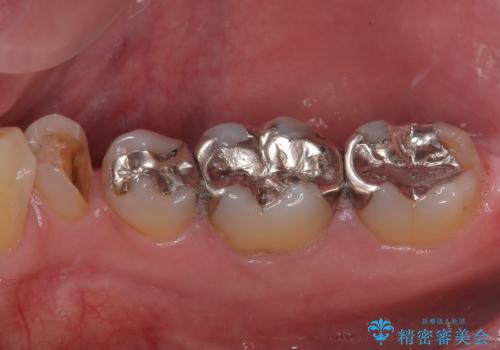

- 右下の銀歯が取れたとのことで来院された患者様です。以前にも取れていたところで、メタルインレーの不適合も認めていたため、次回外れたらオールセラミッククラウンにやり替えていくことを説明していたため、オールセラミッククラウンによる補綴治療を行っていくことにしました。

拡大鏡視野下で虫歯を除去しオールセラミッククラウンに適した形に整えました。

順次、後ろにある不適合のメタルインレーの部位をやり替えていく予定です。